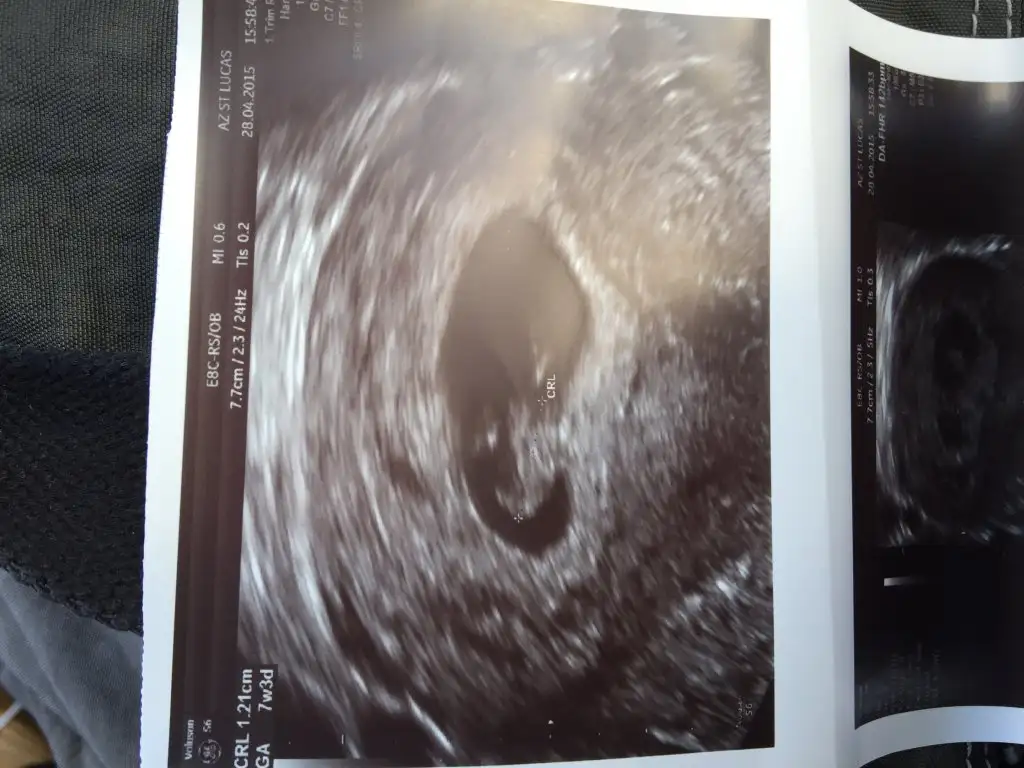

oldugu gibi keseyı kaplamıs :=) sanırım 7-8 hafta ıcın gecerlı

Ee o kadar yiyorum büyüyceq her yeri kaplıycak teyzesi :) bak daha önceki haftayı ekliyorum